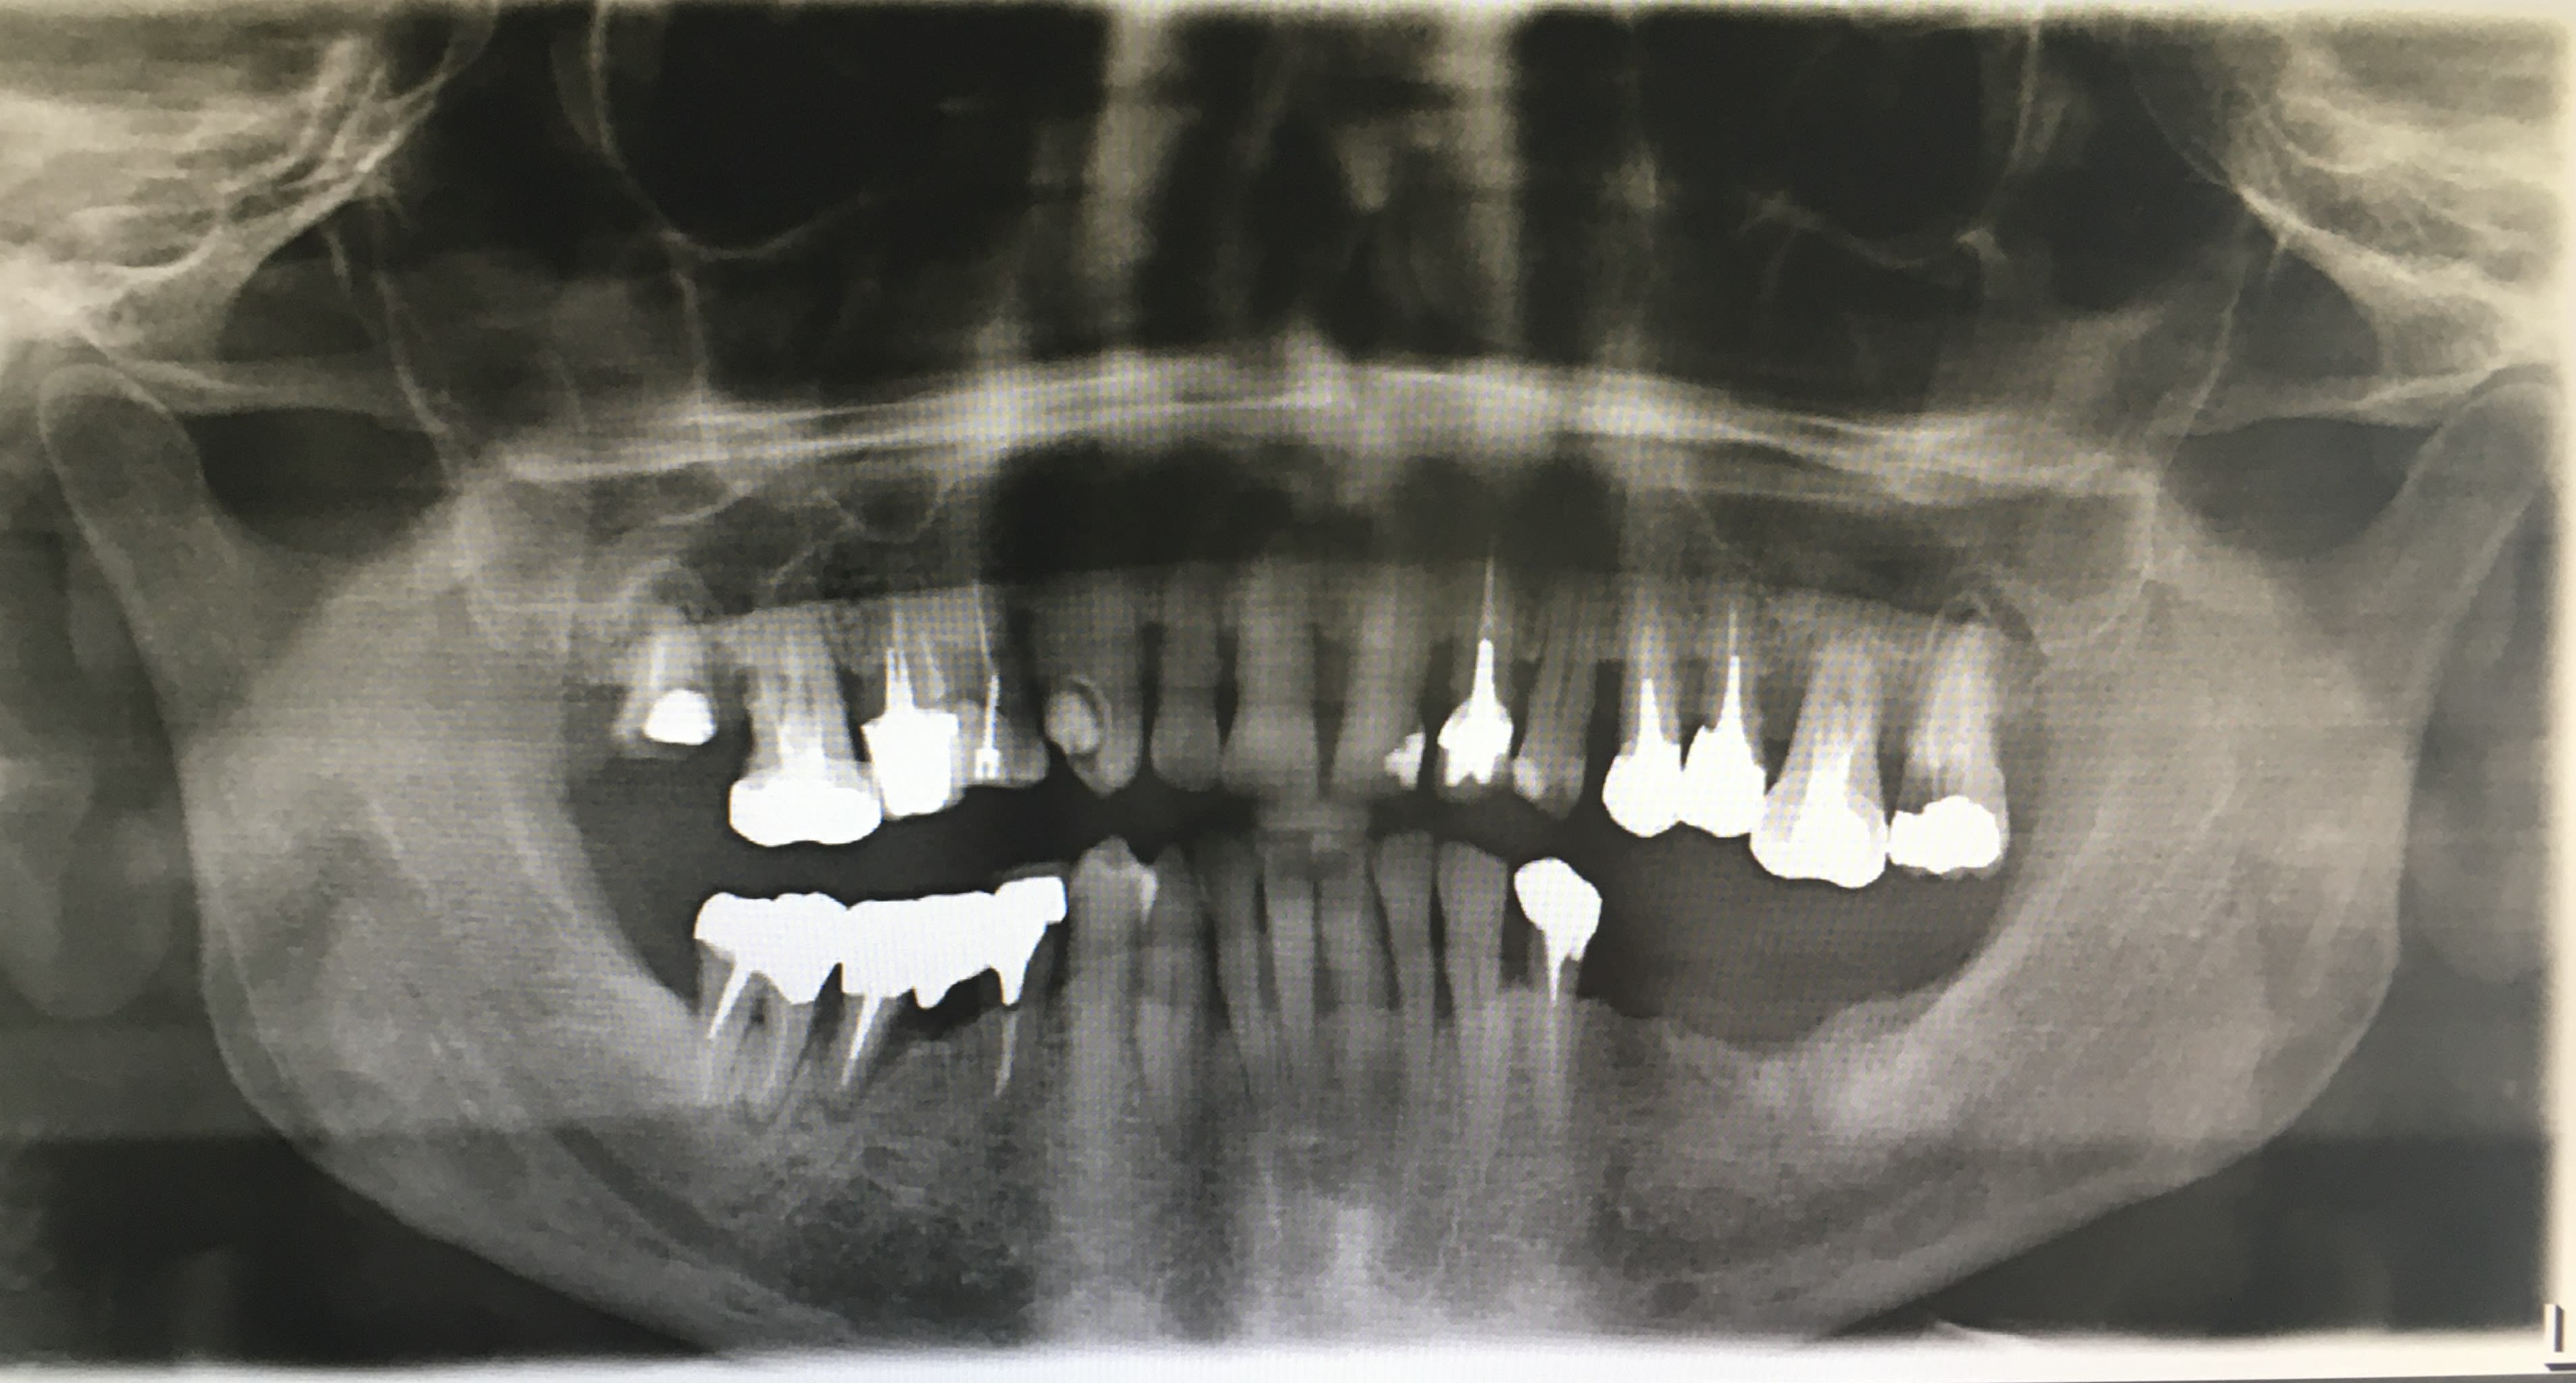

Patient de 62 ans, fumeur, hyper stresse, l’anesthésie qui prend super mal…

Je compte lui proposer - à la posit- un bridge complet à mise en charge immédiate en haut sous AG?

Ainsi que des implants secteur 3

Les pulpects de 13 , 27 et l'extraction de 18(17?) ne vont pas se faire sous AG :-)

- Fumeur ~ 15 cigarettes

- Sous AG : car l’anesthésie prend chez lui super difficilement : les extractions du secteur 3 ont été très penibles

Sous AG, ok, denteo. Mais les deux dents a devitaliser 13 et 27 peuvent etre tres hasardeuses, necessiter peut etre si tu ne trouves pas des canaux, un deuxieme RV long. Et tu dois faire ca avec le stress du temps d'anesthésie generale, avec l'anesthesiste qui regarde sa montre, pffff....

L'extraction de 18 semble fastoche, par contre!

J'ai toujours des doutes face au bridge complet quand toutes les dents sont là. Quand les dents vont bien je me demande pourquoi jumeler; et quand on pourrait se dire que le bridge sert de contention (comme dans ton cas) ce qui semblerait l'indication, je me dit qu'il y a forcément une dent qui va merder dans le tas et nécessiter des bricolages bien moches avec avulsions sous le bridge etc... dans quelques années.

Cela dit vu le patient et si la paro est stabilisée, pourquoi pas.

Qu'est ce que tu appelles anesthésie qui prends mal? A priori on a réussi à lui traiter endo 10 dents, je ne vois pas pourquoi ce que tu prévois ne serait pas possible, surtout si c'est au maxillaire et qu'il te reste peu de dents vivantes.

Effectivement chacun voit le cas sous le filtre de ce qu'il maîtrise le mieux. Pour toi c'est bridge implanto et à part la clope tout semble bien jouable.

Pour moi c'est un jolie cas de restauration conventionnelle complète UNITAIRE Emax avec implanto pour 35 36 45 46 16 26, à équilibrer évidement. Mais quasi sûr que l'implanto totale sera plus pénard à faire !

Le bridge implanto se défends aussi, sans doute autant que bridge sur dents. Par contre la gestion du niveau osseuse va être délicate.

Je comprends mieux l'AG, même si je reste assez réfractaire, mais je ne sais pas à quel point ça a été compliqué pour les avulsions (qui étaient à la mandibule cela dit, c'est toujours plus compliqué).